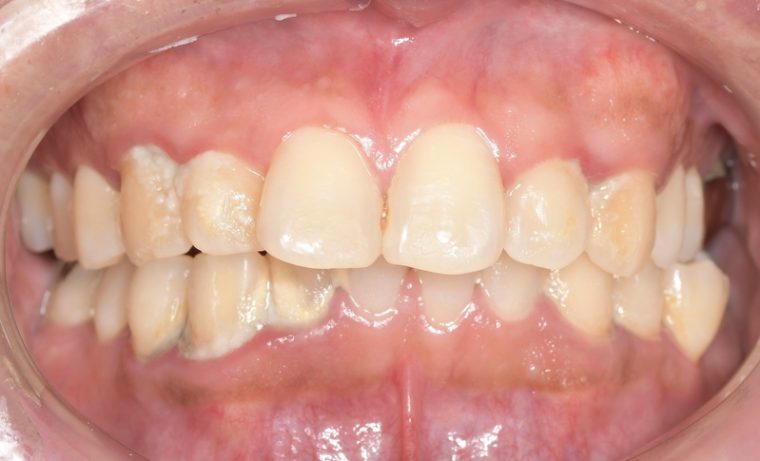

before

症例

after

基本情報

年齢・性別 32歳・男性

主訴 主訴:歯ぐきから出血する

治療部位:全顎

治療内容 「全顎」

歯周基本治療(歯周精密検査、スケーリング、OHI、SRP)

治療期間 約3ヶ月

治療費 歯周基本検査:約600円(保険診療3割負担)

スケーリング、OHI:約2,000円(保険診療3割負担)×2回

SRP、OHI:約1,500円(保険診療3割負担)×4回

歯周精密検査:約1,200円(保険診療3割負担)×2回

合計金額13,000円

(2025年2月現在)

リスク・副作用 歯石を取った後に、歯がしみることがあります。

治療方針 ①検査

レントゲン、口腔内写真を撮影して、歯や歯周組織の状態を確認します。

また、歯周病の検査で歯周ポケットの深さや出血の有無を確認します。

②スケーリング、OHI(口腔衛生指導)

スケーリングをして歯の表面の歯石を除去します。

また、正しい歯磨きの仕方や、フロスの通し方を一緒に確認します。

③歯周精密検査

前回歯石除去と歯磨き指導を行なった結果、歯ぐきの状態がどれぐらい改善したか検査します。

④SRP

歯ぐきの内側についてる歯石を除去します。

⑤歯周精密検査

SRP後、歯周病が改善されたか、検査します。

歯周ポケットが4ミリ以上の部位は、再度SRPを行います。

今回は歯周病の状態が安定したため、3ヶ月おきの定期検診で歯周病の再発や進行を防ぎます。

特記事項 歯周精密検査について:

・歯周ポケットが4ミリ以上ある場合は歯周病で、3ミリ以下は健康な歯ぐきです。

・出血の有無で炎症があるか確認します。

・磨き残しがある部分を確認して記録します。

担当者所見 初診時は、写真を見て分かるように、歯ぐきが赤く腫れていました。

また、歯周病の検査では、全体的に歯と歯の間の部分の歯周ポケットが4ミリあり、全体の約81%から出血が認められました。

出血量も多く、歯ぐきに触れた瞬間に出血しました。

レントゲンで骨のレベルがしっかりとあることが確認できました。

そのため、ご自身で正しい歯磨きを継続することで改善すると考えました。

歯周基本治療を経て、再度検査した結果、歯周ポケットはほぼ3ミリ以下に改善しました。左下7番の残存した歯周ポケットは、隣の親知らずを抜いたため経過観察します。

出血率は約4%まで改善し、出血量も点状で少なくなりました。

今後は右上2番、右下3番の歯ぐきの発赤の改善と、出血率0%を目指して、定期検診でメンテナンスしていきます。